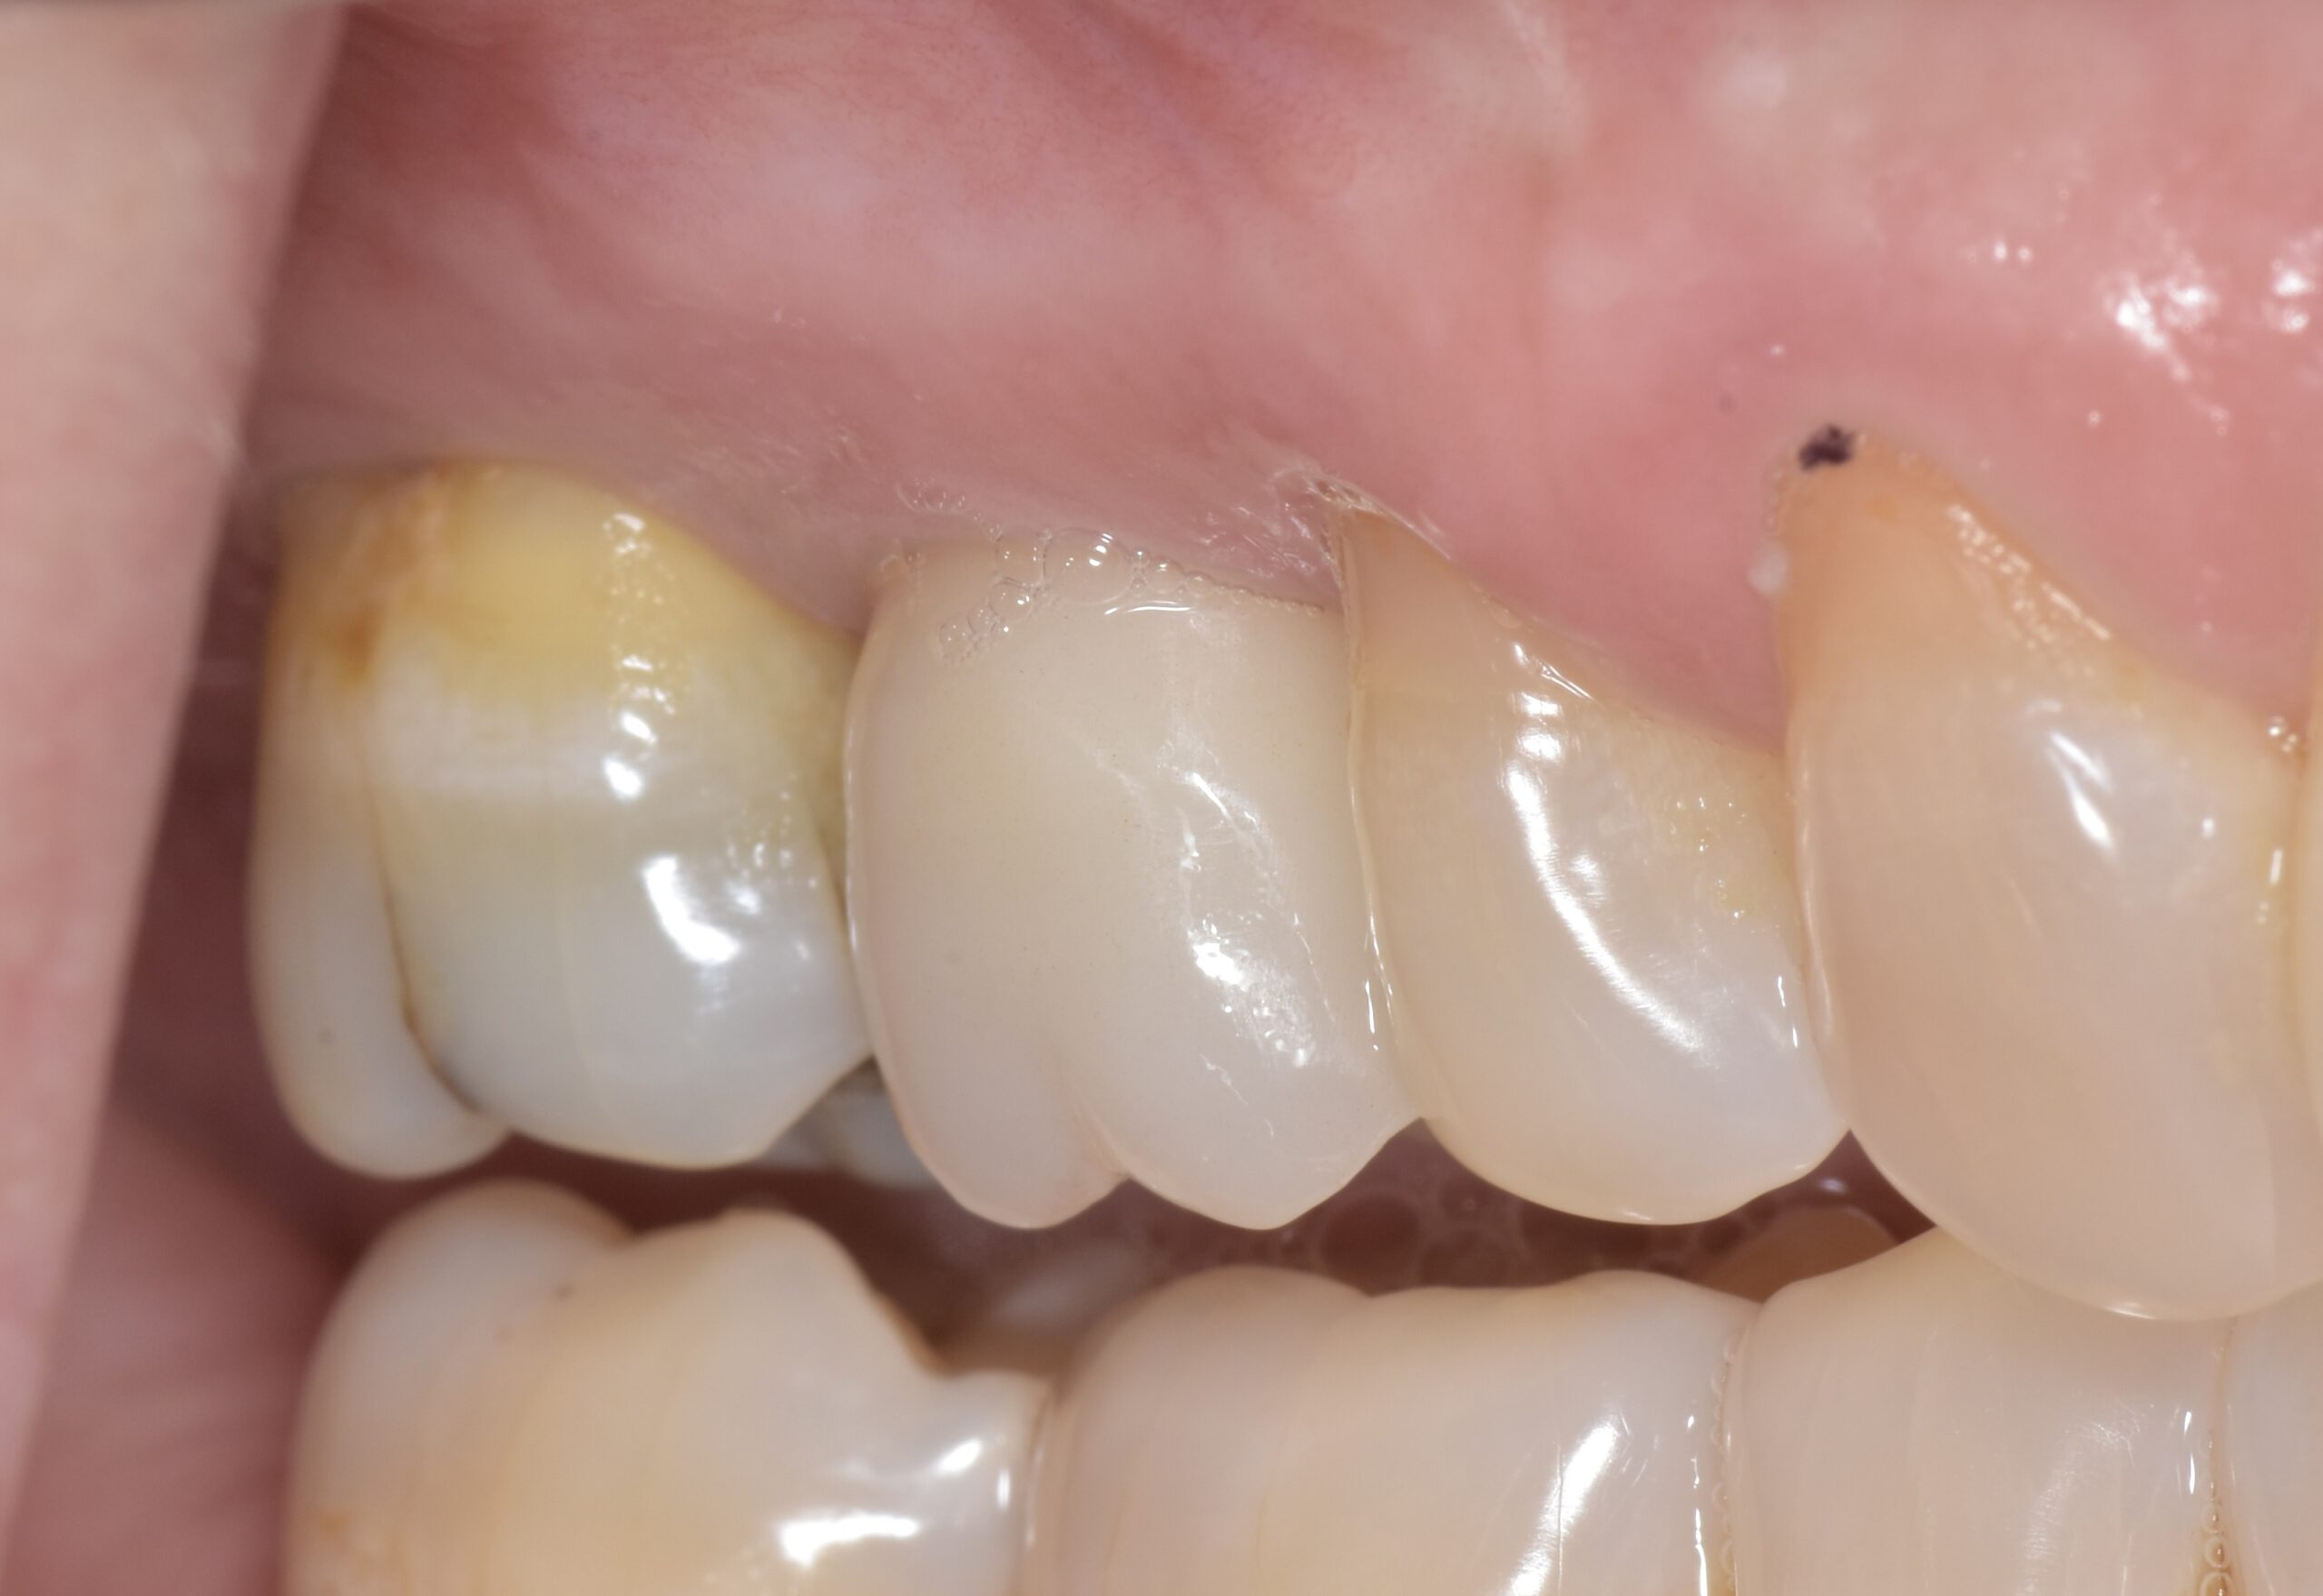

初診時

術後